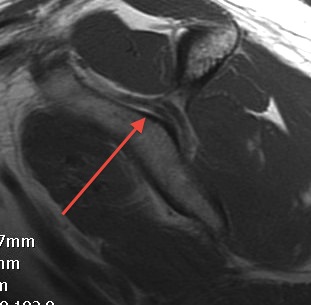

MRI

Spinoglenoid cyst

Spinoglenoid cyst with SLAP tear and posterosuperior labral tear